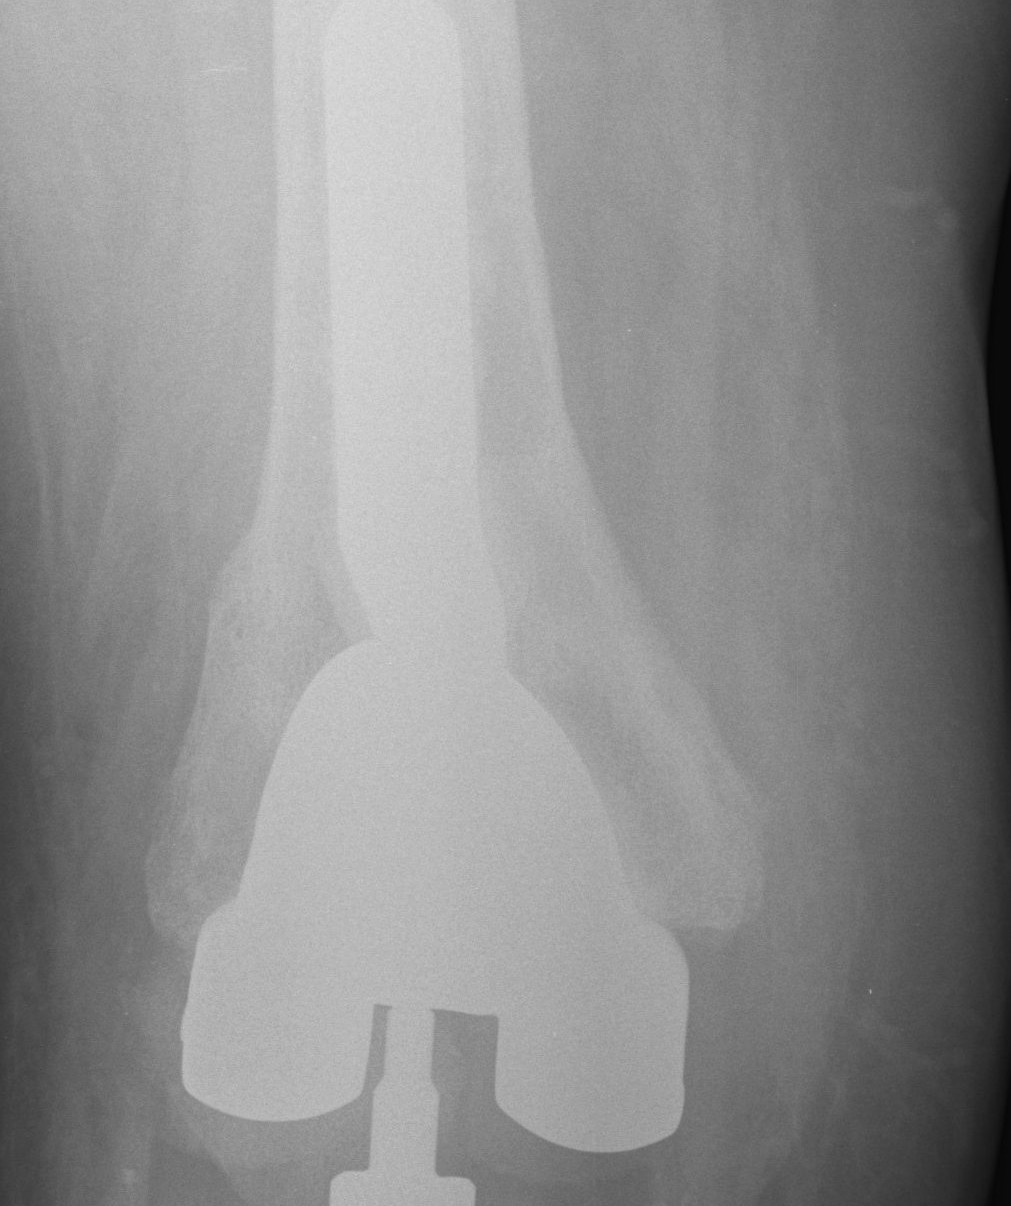

Constraint

Usually determine constraint after bone defects dealt with and flexion / extension gaps balanced

1. Collaterals Intact

Posterior stabilised sufficient

2. MCL deficient

Option B

Rotating hinge

- elderly patient MCL deficient